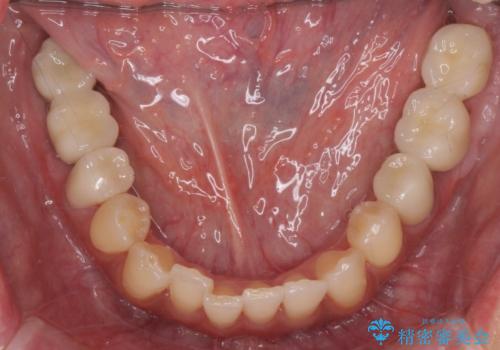

安定する噛み合わせの位置を探りながらの治療となりました。

最終的に非常に安定した咬合関係を構築できたので、しっかりとどんな食事でも楽しめると同時に、清掃性も高く清潔な口腔内環境を確立できました。